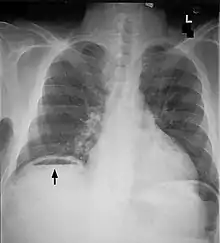

| Frontal chest X-ray. The air bubble below the right hemidiaphragm (on the left of the image) is a pneumoperitoneum. | |